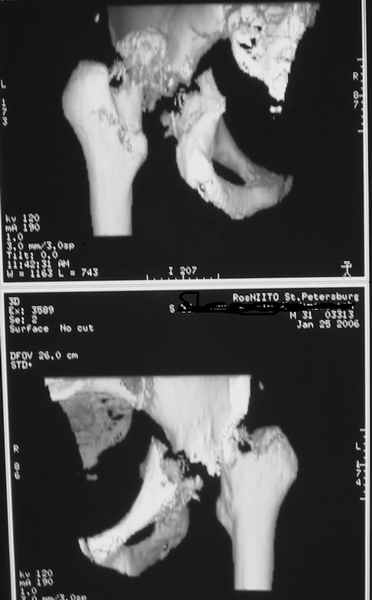

Вариант с постепенной репозицией возможен, у нас такие операции были - аппаратом с введением стержней через вертельную зону в лонно-седалищный фрагмент с подтягиванием его латерально и дистально до максимального контакта задней колонны, затем открытый остеосинтез впадины с заполнением дефекта всем, чем попало. Через 2-3 мес. - эндопротез стандартным доступом, делали винтовую чашку.

Однако, учитывая вывих, 5-месячный срок мы бы, наверно, без аппарата сразу забрались в сустав с целью его реконструкции и остеосинтеза винтами и пластинами. Если удастся сделать остеосинтез хорошо - сразу сделать и эндопротез. Доступ - есссно, не как на протез, а как на впадину - или Y-образный с остеотомией болшого вертела, или латеральный. В случае подозрения на нестабильность впадины после остеосинтеза или больших трудностей при синтезе - засунуть головку во впадину, сделать остеосинтез шейки винтами, и дождаться сращения впадины, попытавшись сохранить движения в суставе. Пишут, можно противопротрузионными кольцами или Octopus укрепить остеосинтез впадины, и тогда тоже делать протез сразу, но у нас такого опыта нет, в основном предпочитали делать в два этапа - сначала реконструкция впадины, потом протез, потому что в застарелых случаях впадина сильно кривая.

Здравствуйте. Разрешите предложить вам следующий вариант: Доступ- задний типа Кохера, с возможным отсечением большого вертела. Репозиция поперечного перелома впадины (насколько возможна), остеосинтез реконструктивной пластиной. В случае большого деффекта заднего края и крыши- пластика фрагментом головки бедра. Ацетабулярный компонент- реконструктивное кольцо. Есть вариант одномоментного остеосинтеза впадины на кольце типа Bursch-Shneider с фиксацией дистального лепестка кольца к седалищной кости.Желаю успехов.

Поэтому скорее всего я бы планировал открытую репозицию и фиксацию перелома впадины илеофеморальным или задним доступом с одномоментным протезированием( укрепляющее кольцо + бесцементный бедренный компонент).